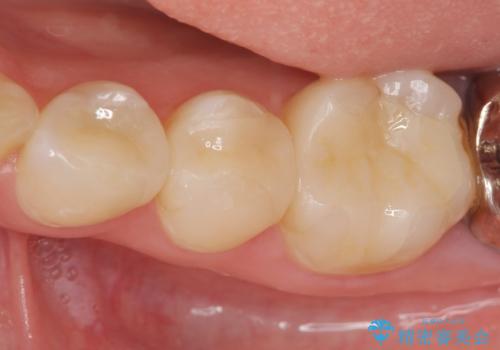

天然の歯のような色調を再現したセラミック修復処置を行ったことで口腔内の目立つ銀歯がなくなり満足いただくことができました。